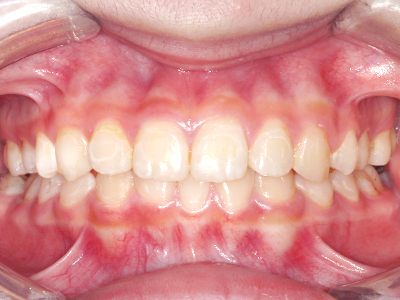

ないき歯科クリニックでは、これからあごが成長していくお子様や、歯並びが気になる成人の方など、さまざまな年代の方に対して矯正治療を行っています。

歯並びやかみ合わせを正しく整えると、笑顔や発音の自信につながり、むし歯・歯周病・口臭の予防にも役立ちます。

ないき歯科クリニックでは、上あごの成長不足を補い、鼻呼吸を獲得しつつ歯列を整え、将来のお口をより健康な状態にすることをゴールに定める矯正治療をおこなっています。